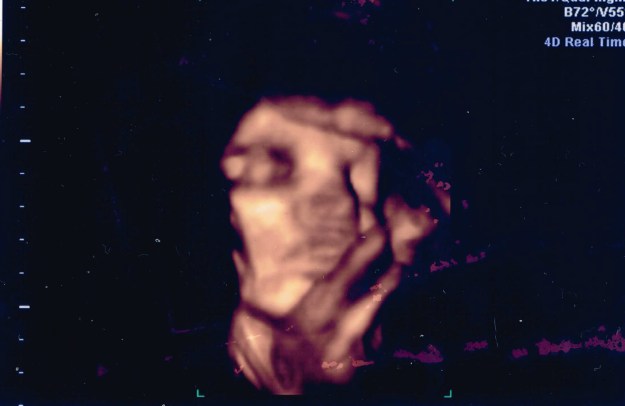

13 - 33SA

Un visage, derriere un bras – 33SA.